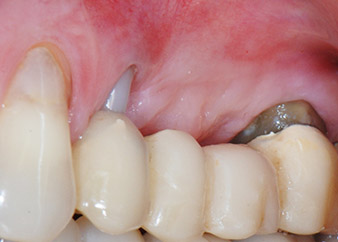

Resultado provisional a los 2 meses

Las figuras 17 y 18 muestran el resultado clínico 2 meses después de la intervención quirúrgica. La pieza 24 tenía una movilidad reducida clase I de Miller y los tejidos blandos no presentaban inflamación. Se evitó el uso de una sonda en este momento para evitar una nueva infección y para no romper la fijación epitelial. El siguiente control se planificó para el momento en el que se reanudara el tratamiento y se colocaran los pilares de cicatrización, 6 meses después de la inserción de los implantes.